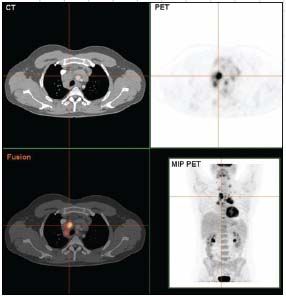

Twenty-five years later the situation has changed dramatically-and much to the benefit of our patients. Our understanding of these diseases has improved considerably since the WHO classification created clear definitions for diagnoses and began to recognize many entities that were not known (and thus not well treated) a quarter of a century before. PET scanning is having a major impact on the care of patients with lymphoma-more by improving the ability to recognize a complete response than by altering staging. Today most patients with diffuse large B-cell lymphoma are cured, with the most important recent advance being the availability of rituximab. Rituximab has also had an important impact on the management of patients with follicular lymphoma, not just in terms of duration of response, but in terms of improvements in survival. Estimates of median survival for patients with low-grade follicular lymphoma who receive rituximab as part of their initial therapy (and often as a maintenance treatment) are approaching 20 years. The peripheral T-cell lymphomas are finally being studied as specific entities: we know that anaplastic large-cell lymphoma that over-expresses the ALK protein is associated with a good survival, but better regimens are still desperately needed for patients with the other subtypes. Finally, Hodgkin lymphoma is now curable in the great majority of patients, and the focus of current studies is to reduce long-term toxicity without sacrificing the high cure rate.